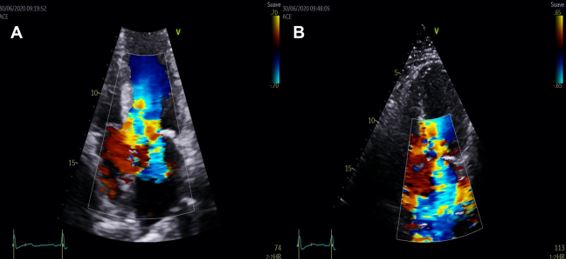

Mitral regurgitation (MR) may be influenced by secondary or primary mechanisms. Whereas MR due to annulus dilation or intrinsic valve disease may be central or anterior-directed, MR in context of SAM usually has a mid-to-late systolic onset, which interferes with the assessment of LVOTO5.

The mechanisms of MR in HCM include SAM with failure of leaflet coaptation, elongated mitral leaflets coapting in the leaflet body, anterior displacement of the mitral apparatus and PM. The anterior leaflet of the mitral valve behaves as an anterior prolapse and this arrangement in systole generates a typically mid-to-late onset eccentric lateral and posterior MR jet. Quantification of MR severity should be performed according to published recommendations and its dynamic components evaluated with provocative manoeuvres or EE3 (Figure 3).

Colour Doppler is useful to initially locate the level at which the obstruction occurs, as aliasing will occur where there is flow acceleration. To measure LV outflow tract and intraventricular gradients, continuous Doppler is used to measuring the degree of obstruction and pulsed Doppler to locate the exact point where the obstruction is occurring, since depending on the different patterns of ventricular hypertrophy, the obstruction may occur at different levels. It is therefore advisable to use pulsed Doppler from the apex to the base and outflow tract so as not to miss possible intraventricular areas of increased gradients. The typical morphological appearance of the Doppler signal is a “dagger-shaped” and late peaking curve. This is because HCM creates a vicious circle in which obstruction generates more obstruction. At the beginning of systole, ejection begins normally but as systole progresses the outflow tract narrows due to increased pressure and the pressure increases further due to the narrowing of the outflow tract thus closing the circle. Thus, the continuous Doppler contour shows a progressive flow acceleration pattern (Figure 3).